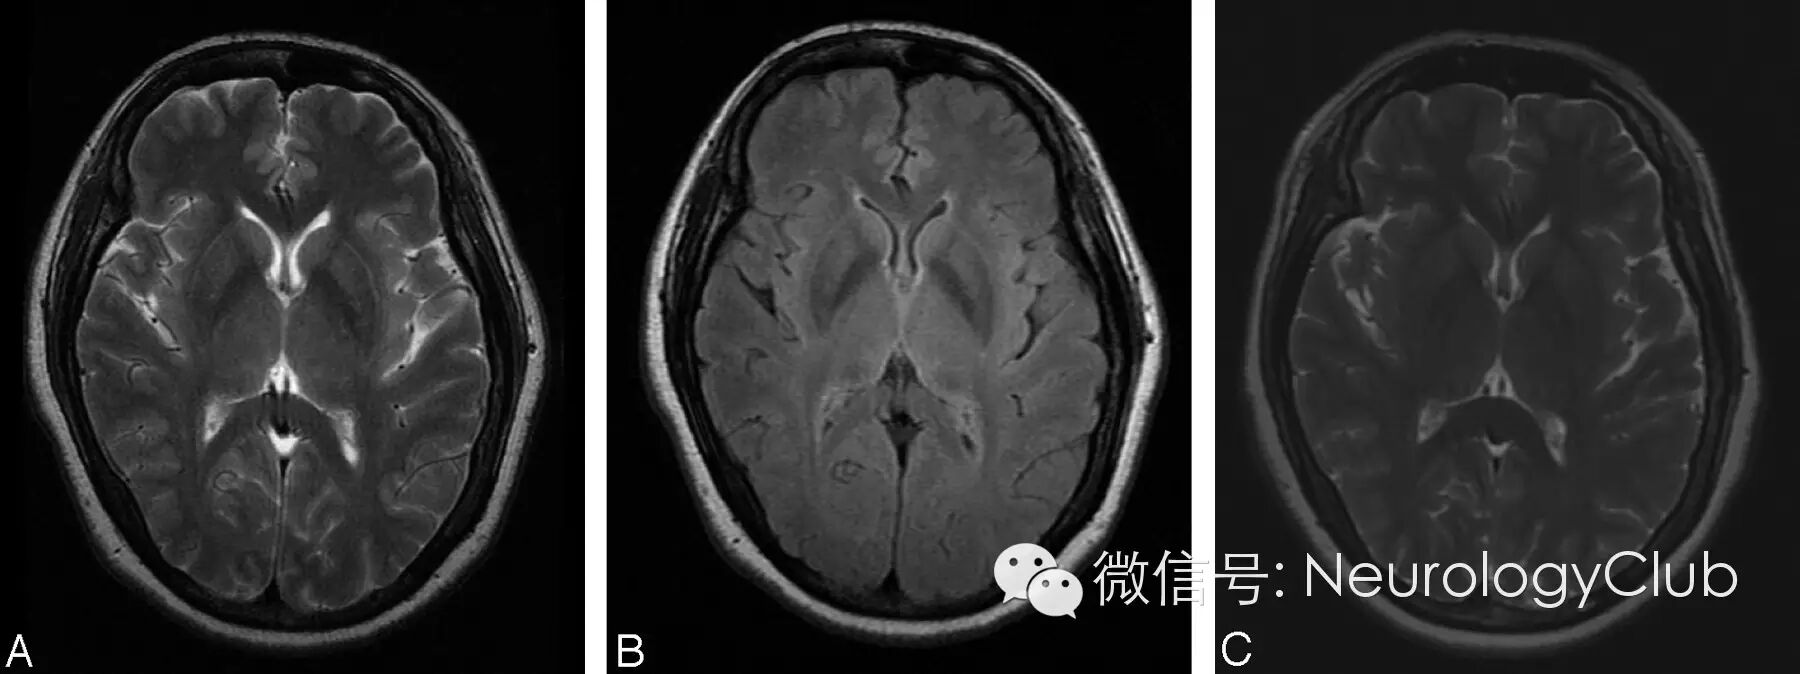

裂隙征(间隙征,Slit-like hyperintensity sign

指壳核外侧边缘T2WI高信号环Hyperintense Putaminal Rim Sign,是MSA-P在1.5T MRI上的一个特征性征象。其病理基础还不是很确定,有学者认为是由于壳核外侧神经元缺失以及胶质增生,壳核萎缩引起组织问空隙增大产生的。但在3.0T MRI检查中,壳核“间隙征”亦可见于帕金森患者以及健康人。

(65岁女性,诊断为MSA-P)

46岁健康女性。A-B:3T MRI纹状体水平T2WI和FLAIR可见双侧壳核外侧缘高信号,即裂隙征。C:1.5T MRI上未见异常。